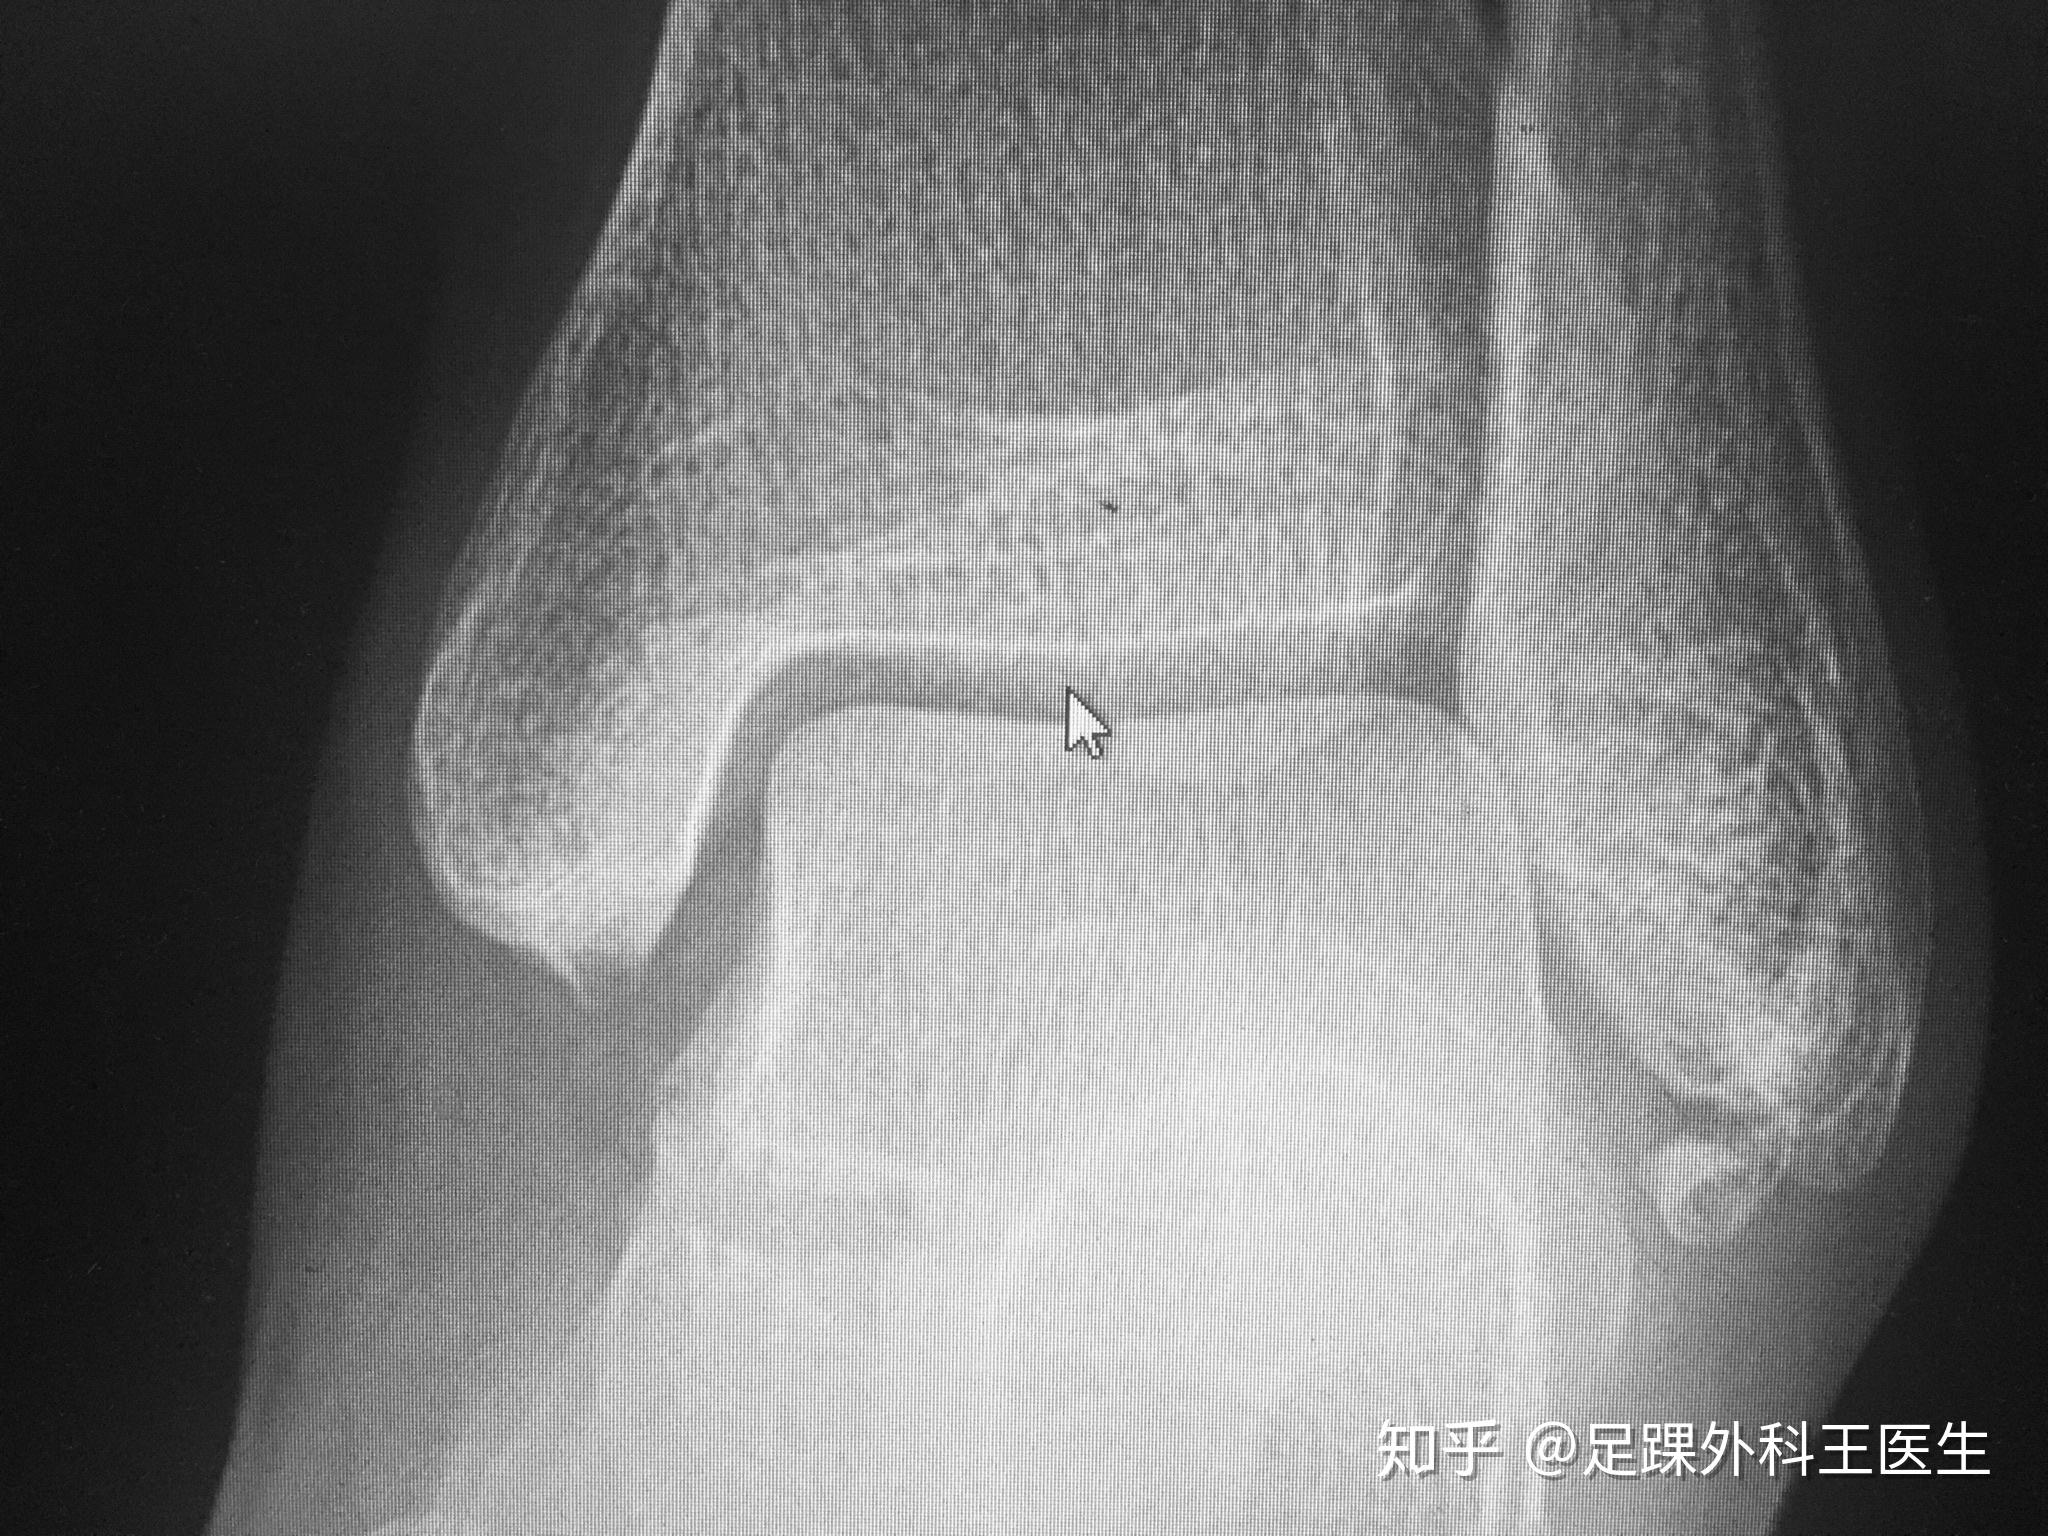

请问左脚胫距关节间隙在哪儿

图片尺寸2048x1536